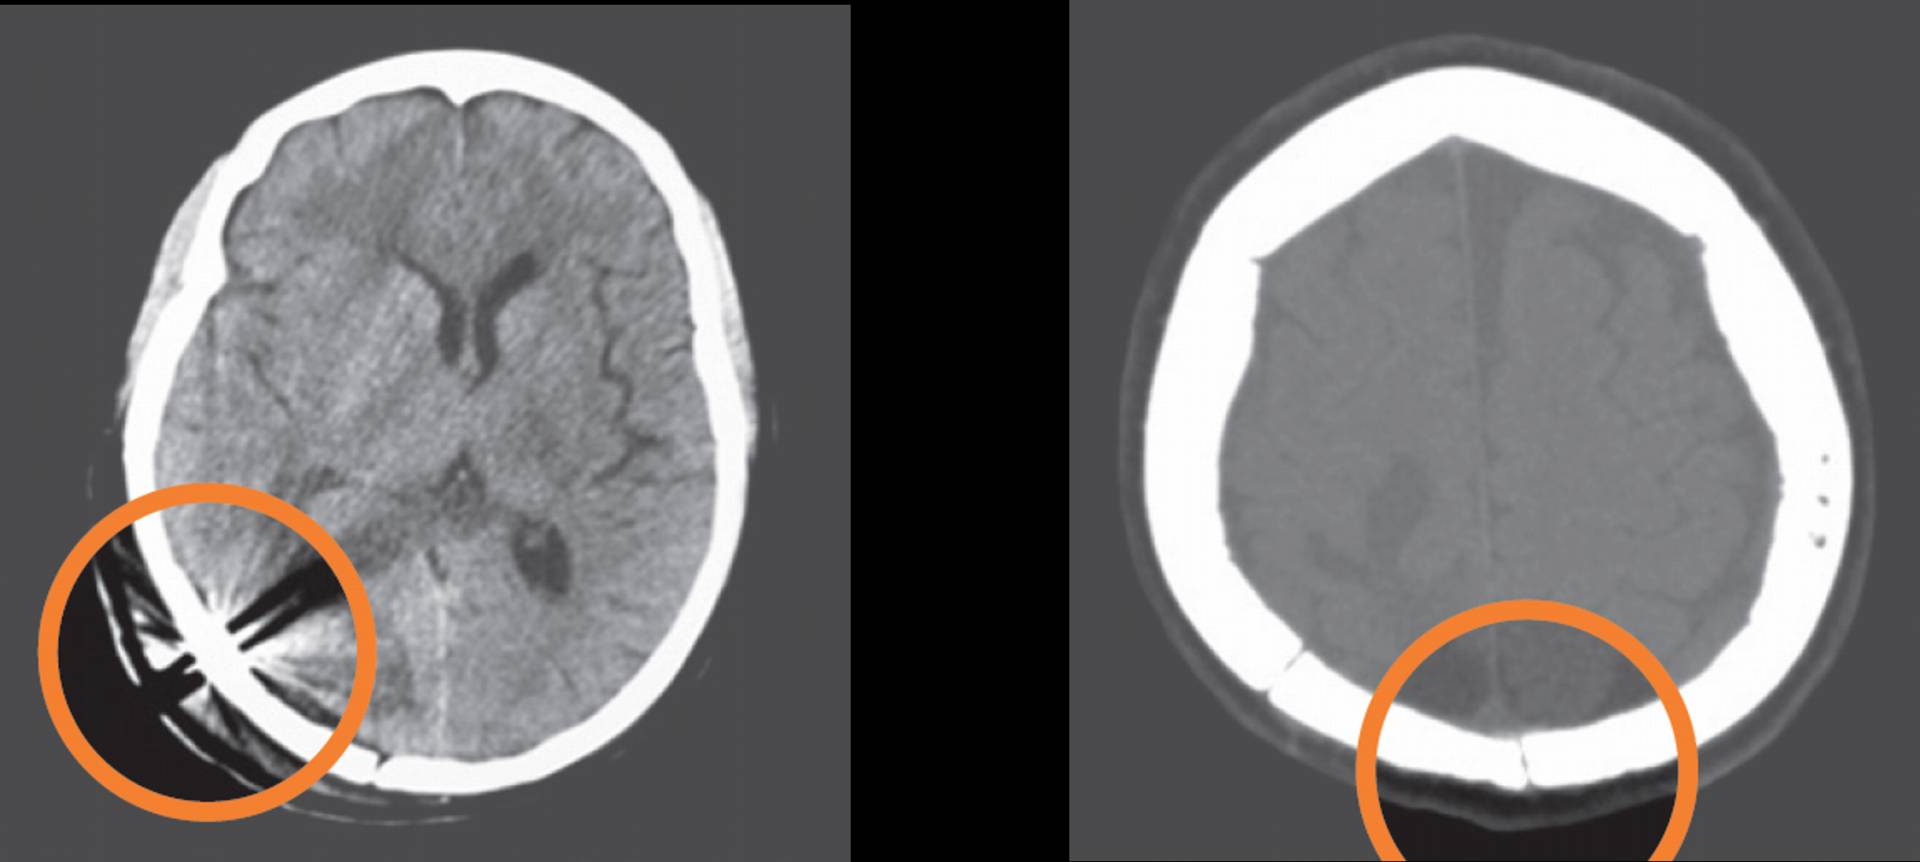

アーチファクトを引かないので画像診断に優れる

PEEK製のためCT、MRI撮影時のアーチファクトがない